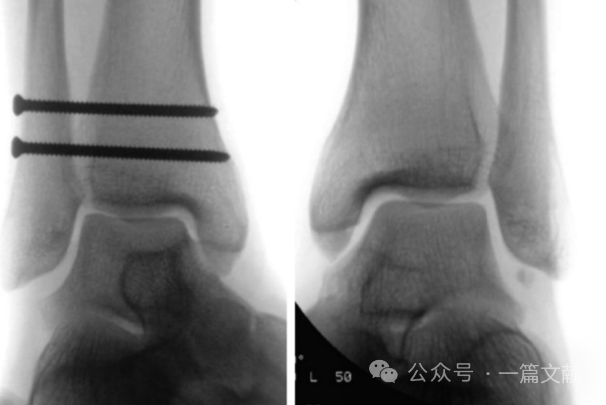

螺钉最终固定的踝穴位片与健侧相对比如下图: